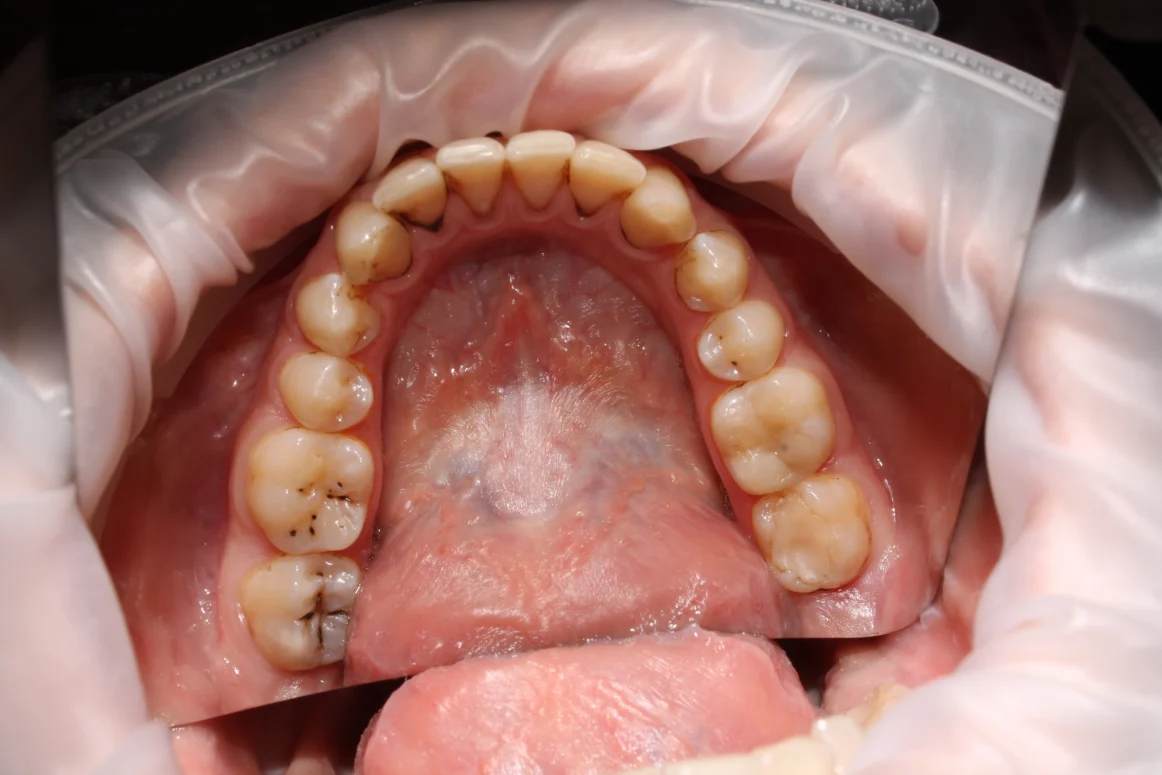

- White or dark spots on the surface of the tooth

- Visible holes or pits in the teeth

A dentist removes the decayed part of the tooth and fills it with a restorative material. This prevents the growth of bacteria and restores the tooth structure and function. Cavities are usually identified during a dental check-up using visual examination and, when needed, X-rays to confirm early damage. - Root Canal Treatment If the tooth decay reaches the pulp, you may need a root canal treatment.